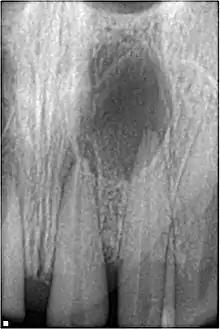

Radiographic signs of periapical inflammation is usually evident in a tooth with necrotic pulp

Pulp necrosis usually occurs either as ischaemic necrosis (infarction) caused by disruption to the blood supply at the apical foramen or as an infection-related liquefactive necrosis following dental trauma (2). Signs of pulpal necrosis include[40]

• Persistent grey colour to tooth that does not fade

• Radiographic signs of periapical inflammation

• Clinical signs of infection: tenderness, sinus, suppuration, swelling

Treatment options will be extraction for the primary tooth. For the permanent tooth, endodontic treatment can be considered.